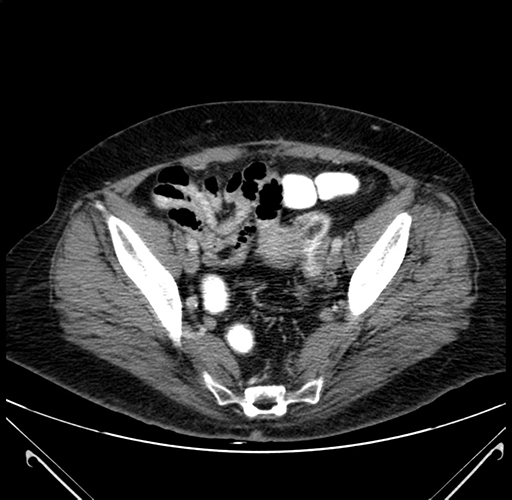

Axial Venous